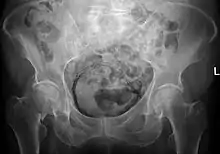

Emphysematous cystitis